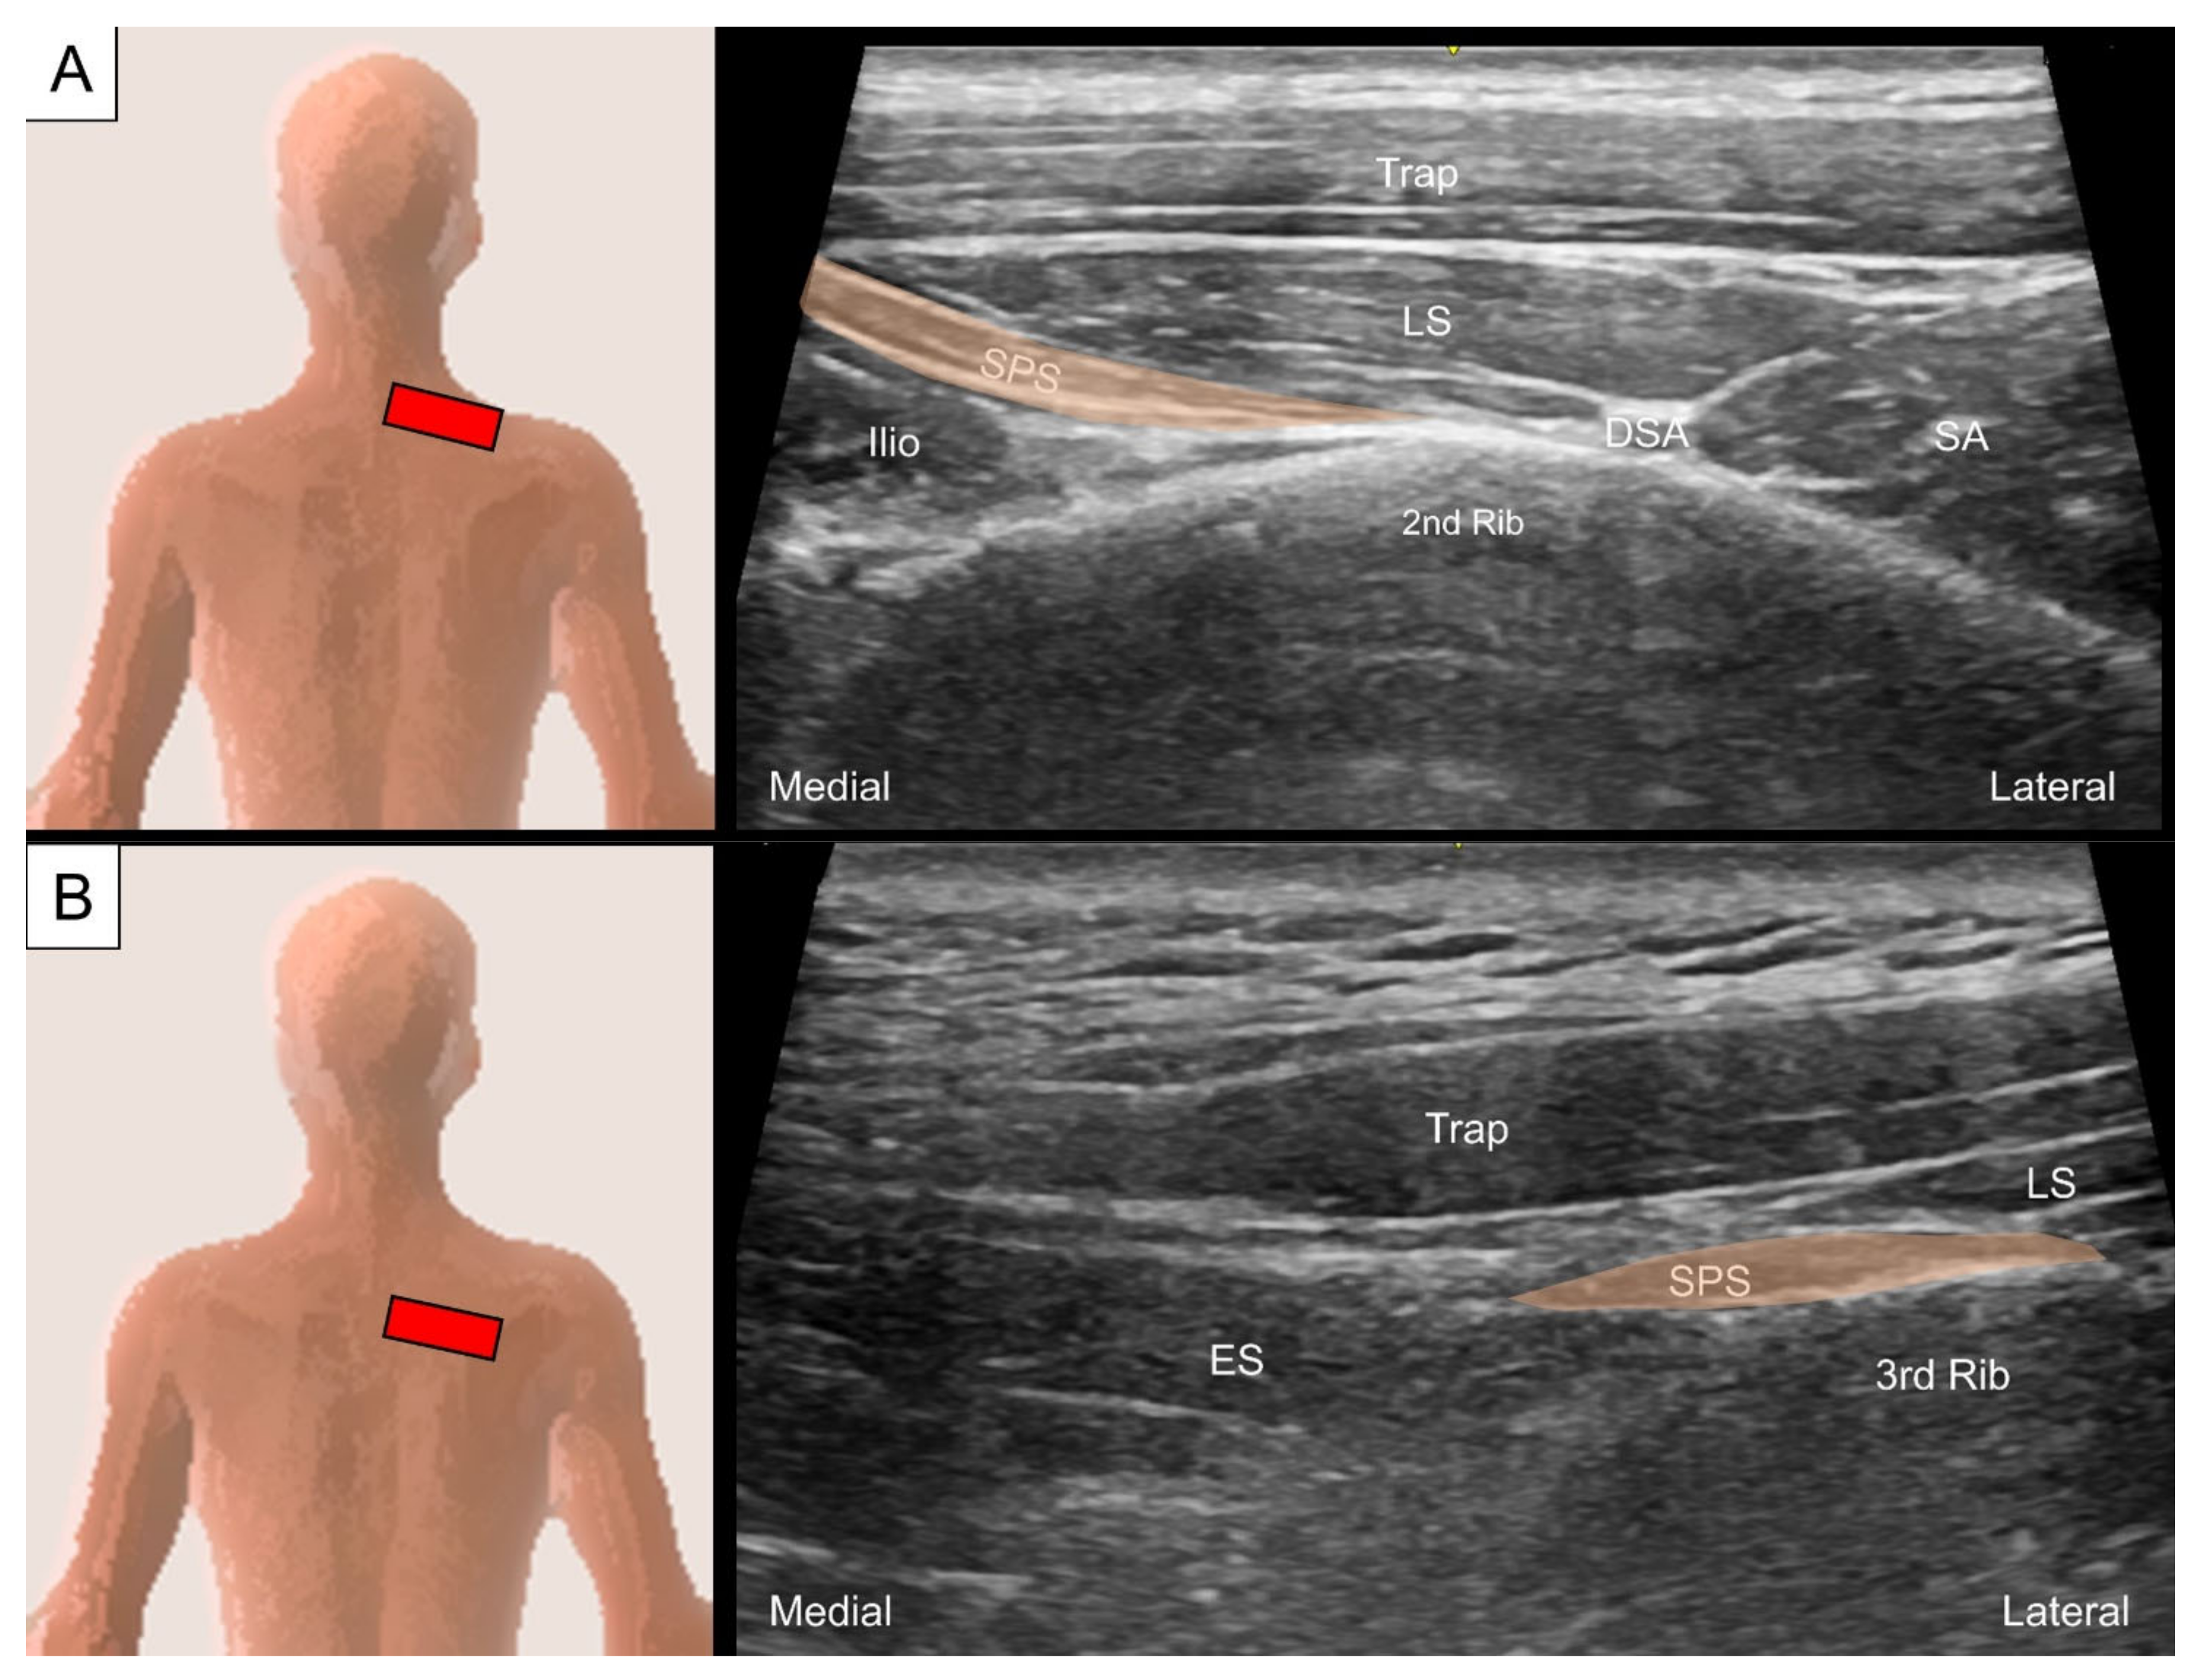

3.1. Serratus Posterior Superior/Inferior

3.1.1. Anatomy

3.1.2. Sonographic Scanning

3.1.3. Clinical Relevance